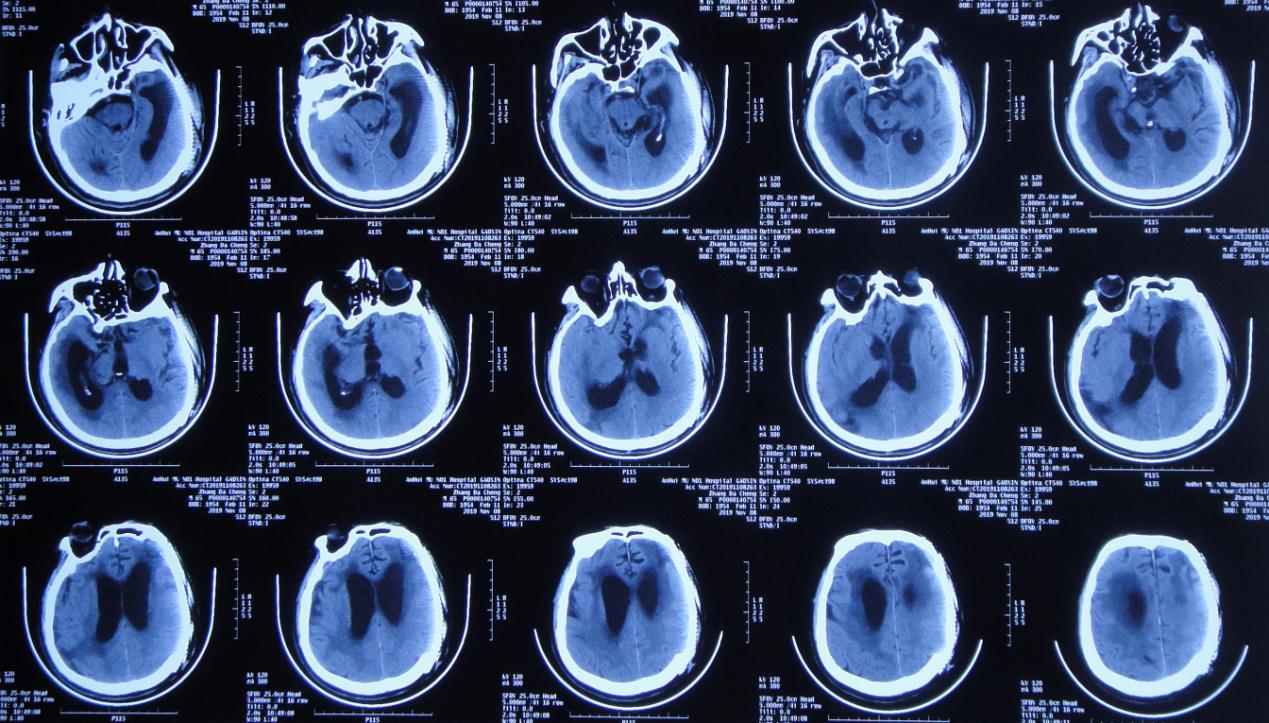

更换脑室外引流管后第14天,颅骨修补术后第70天,左颞叶血肿清除+去骨瓣减压术后第176天,即2020年 1月2日,行脑室腹腔分流术(术中拔除原脑室外引流管)。术后第2天复查头颅 CT( 图-11 )呈脑室腹腔分流术后改变。

图-11: 2020年1月4日术后头颅CT

脑室腹腔分流术后第5天,颅骨修补术后第75天,左颞叶血肿清除+去骨瓣减压术后第181天,即2020年 1月7日患者出现高热,体温39.1℃,复查头CT头颅( 图-12 )与2020年1月4日对比未见明显变化。

图-12: 2020年1月7日头颅CT

但腰大池置管引流术后第9天,即2020年1月16日,突然呈昏迷状态,急查头颅CT( 图-13 )较2020年1月7日未见明显变化。

图-13: 2020年1月16日头颅CT

腰大池持续引流,药物抗感染及鞘内注射等治疗。但患者仍有低热,呈昏迷状态。腰大池置管术后第10天,即2020年1月18日,复查头颅CT( 图-14 )较前仍未见“异常”。

图-14: 2020年1月18日头颅CT

为预防腰大池引流管感染,于腰大池置管术后第12天给予拔除。腰大池置管拔除术后第3天即2020年1月23日,复查头颅CT( 图-15 )较2020年1月18日未见明显变化。

图-15: 2020年1月23日头颅CT

入院时:体温高达38.9℃,呈昏迷状态,疼痛刺激时四肢未见活动;颈稍抵抗,双下肢Babinski征未引出( 图-16 );头颅CT( 图-17 )示脑室腹腔分流术后改变,脑室扩张,脑室周围水肿。

图-17: 2020年1月31日头颅CT

入院第2天,即2020年2月1日行右侧脑室外引流术,术中拔除原脑室腹腔分流管,术后当日复查头颅CT( 图-18 )呈术后改变。

图-18: 2020年2月1日头颅CT术后

经过17天的治疗,于2020年2月18日行脑室腹壁外引流术,术后当日复查头颅CT( 图-21 )呈脑室引流术后改变,脑室较前缩小,脑室周围水肿减轻。

图-21: 2018年2月18日术后头颅CT

2020年4月27日,复查头颅CT( 图-23 )示脑室系统基本恢复正常。于2020年4月28日(即入院第88天,脑室外引流术第87天,脑室腹壁外引流术后69天)行脑室腹腔分流术,术后病情恢复良好。

图-23: 2020年4月27日头颅CT

经过李小勇脑脊液科98天的精心治疗,患者于2020年5月8日出院。出院前查头颅CT( 图-24 );出院时已能独立行走( 图-25 )。

图-24: 2020年5月7日出院前头颅CT